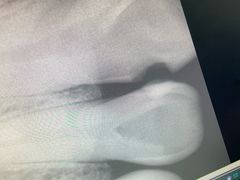

• 上海交通大学医学院附属瑞金医院(总院)

• 全部图片

• 全部图片»

• 环境(149)»

• 其他(102)»